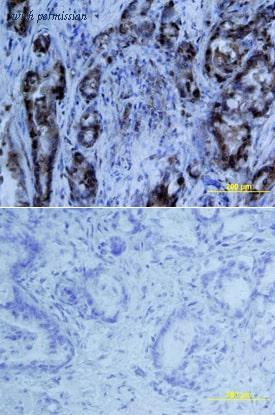

gene information - human MIA

- synonym:CD-RAP

- description:MIA SH3 domain containing